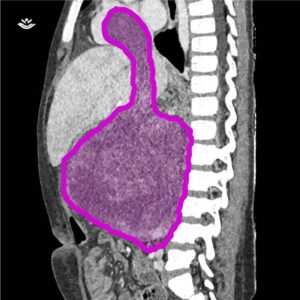

Fetița a fost diagnosticată cu un tip de cancer renal cunoscut sub numele de tumoră Wilms, iar masa tumorală a crescut atât de mult încât i-a ajuns la inimă. Din acest motiv, medicii au fost obligați să intervină în mai multe etape, astfel încât să poată curăța foarte bine toată zona.

Tratamentul aplicat în acest caz complex nu s-a bazat doar pe măiestria chirurgilor, ci a implicat utilizarea unor tehnici de imagistică de ultimă generaţie pentru a realiza o reconstrucţie 3D a masei tumorale ce urma să fie îndepărtată. A fost necesară colaborarea unei echipe multidisciplinare formate din oncologi, chirurgi, cardiologi, anestezişti şi specialişti în imagistică medicală.

Foto: Spitalul Bambino Gesu